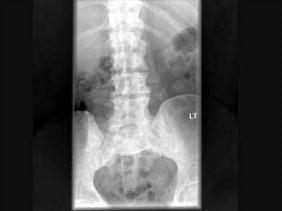

问题 男,77岁,全身性骨痛,夜间加重,贫血,PSA大于100,结合图像,最可能的诊断是?(?)

选项 A.成骨性骨转移 B.多发性骨髓瘤 C.慢性化脓性骨髓炎 D.骨肉瘤 E.以上都不是

答案 A